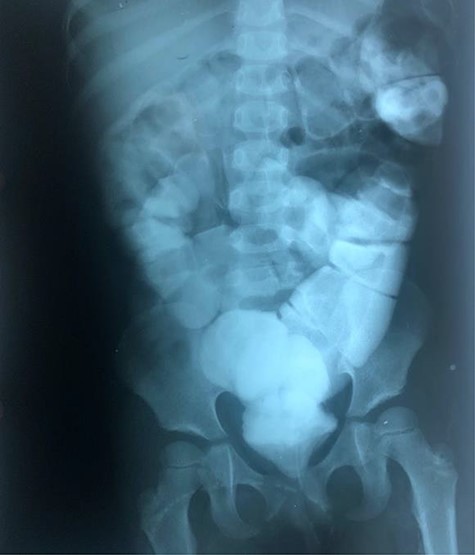

The clinical case consisted of a 4-year-old female patient who presented with long-standing constipation, which afflicted her since birth. The mother referred that the patient could only defecate 2 to 3 times per week, requiring the administration of rectal enemas, lactulose and plum juice. Upon physical examination, the patient presented increased frequency of intestinal sounds, no abdominal tenderness on palpation, tympanic sound to percussion, abdominal distention and a positive blast sign. A water-soluble contrast enema was performed to evaluate the colonic segments and rectum. The study displayed a distal narrow segment with proximal distention representing the pathognomonic transitional zone (Figs 1 and 2). Rectal biopsies were taken at 3, 5 and 10 cm from the anal margin. The biopsy at 3 cm showed hyperplasia of the muscularis mucosae and absence of the submucosal and myenteric nerve plexuses. However, the other two segments that were taken showed no abnormal findings. According to these findings, the patient was diagnosed with USHD. Treatment consisted of transanal myectomy of the internal anal sphincter.

Radiographic abdominal anteroposterior projection of water-soluble contrast enema.